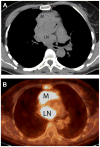

This overview of the 4th edition of the World Health Organization (WHO) Classification of thymic tumors has two aims. First, to comprehensively list the established and new tumor entities and variants that are described in the new WHO Classification of thymic epithelial tumors, germ cell tumors, lymphomas, dendritic cell and myeloid neoplasms, and soft-tissue tumors of the thymus and mediastinum; second, to highlight major differences in the new WHO Classification that result from the progress that has been made since the 3rd edition in 2004 at immunohistochemical, genetic and conceptual levels. Refined diagnostic criteria for type A, AB, B1-B3 thymomas and thymic squamous cell carcinoma are given, and it is hoped that these criteria will improve the reproducibility of the classification and its clinical relevance. The clinical perspective of the classification has been strengthened by involving experts from radiology, thoracic surgery, and oncology; by incorporating state-of-the-art positron emission tomography/computed tomography images; and by depicting prototypic cytological specimens. This makes the thymus section of the new WHO Classification of Tumours of the Lung, Pleura, Thymus and Heart a valuable tool for pathologists, cytologists, and clinicians alike. The impact of the new WHO Classification on therapeutic decisions is exemplified in this overview for thymic epithelial tumors and mediastinal lymphomas, and future perspectives and challenges are discussed.